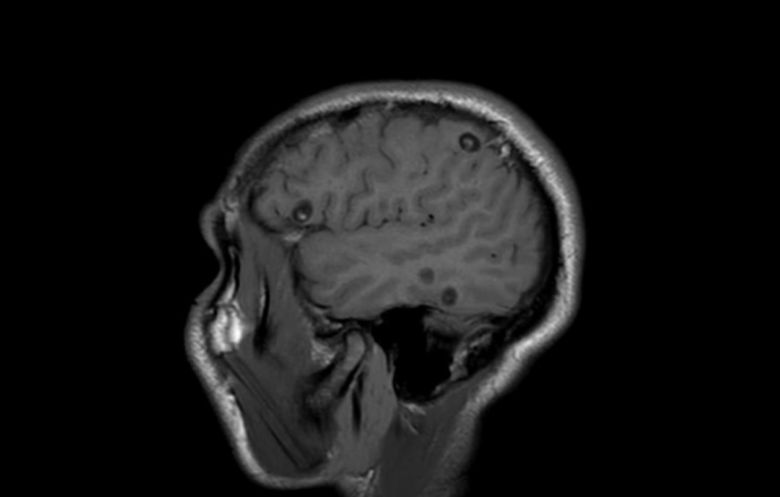

상황이 심각해지자 의료진은 뇌 상태를 면밀히 관찰해 보기로 했다. MRI 검사 결과 목과 얼굴, 혀에서 이상한 반점이 발견됐다. 간과 척추 등 온몸 곳곳에서도 비슷한 병변이 관찰됐다.

'TE'라는 여성의 뇌 MRI 결과 이상한 반점이 발견됐다. [유튜브 Chubbyemu] |

하지만 여성의 몸에 소 촌충만 있는 것이 아니었다. 극심한 두통을 일으킨 것은 바로 돼지고기에서 흔히 발견되는 갈고리촌충이었다. 이 촌충의 알은 장에서 빠져나와 피부에 딱딱한 혹처럼 느껴지는 낭종을 형성한다. 유충은 일반적으로 해롭지 않지만 뇌로 침투하면 두통과 발작 등 심각한 증상을 유발할 수 있다.